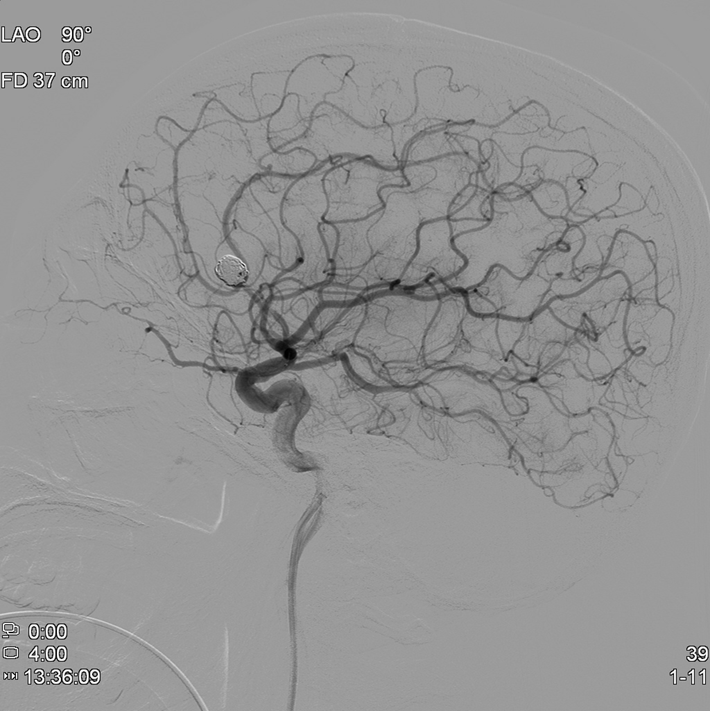

뇌혈관조영술로 동맥류에 대해 정밀검사

혈관내 코일색전술을 통해 개두술 없이 동맥류를 치료함